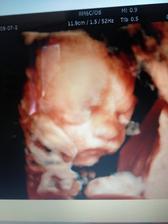

autor@nikuskanaj87 tak ono sa podarilo velmi rychlo,az 2x len bohuzial v oktobri minuleho roka som o mimi prisla,tak verim ze tentoraz sa dockam vonaveho babetka v decembri☺️dakujeeem